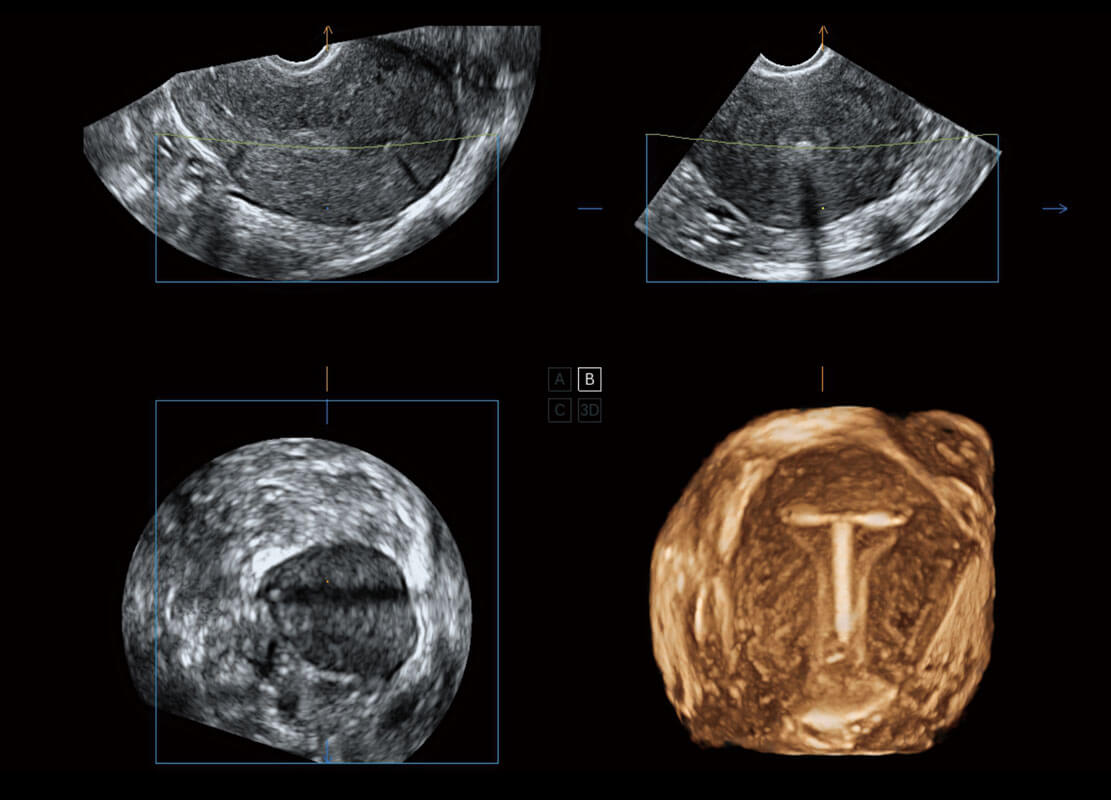

• 腔内三维-宫内节育器

• 腔内三维-光影成像

盆底超声

P60为盆底超声检查提供应用方案,多种腔内及腹部容积探头提供从二维、三维到四维的优异图像品质,实时快速三维容积数据获取,专业的测量工具包等人性化设计,为超声医生诊断提供有力保障。

S-Pelvic

能够简化盆底检查的操作流程,可在二维模式及三维成像模式下实现一键自动提取出标准切面、自动识别当前切面、自动测量,提升盆底检查的高效性,同时也能让青年医生快捷的获得准确的检查结果。